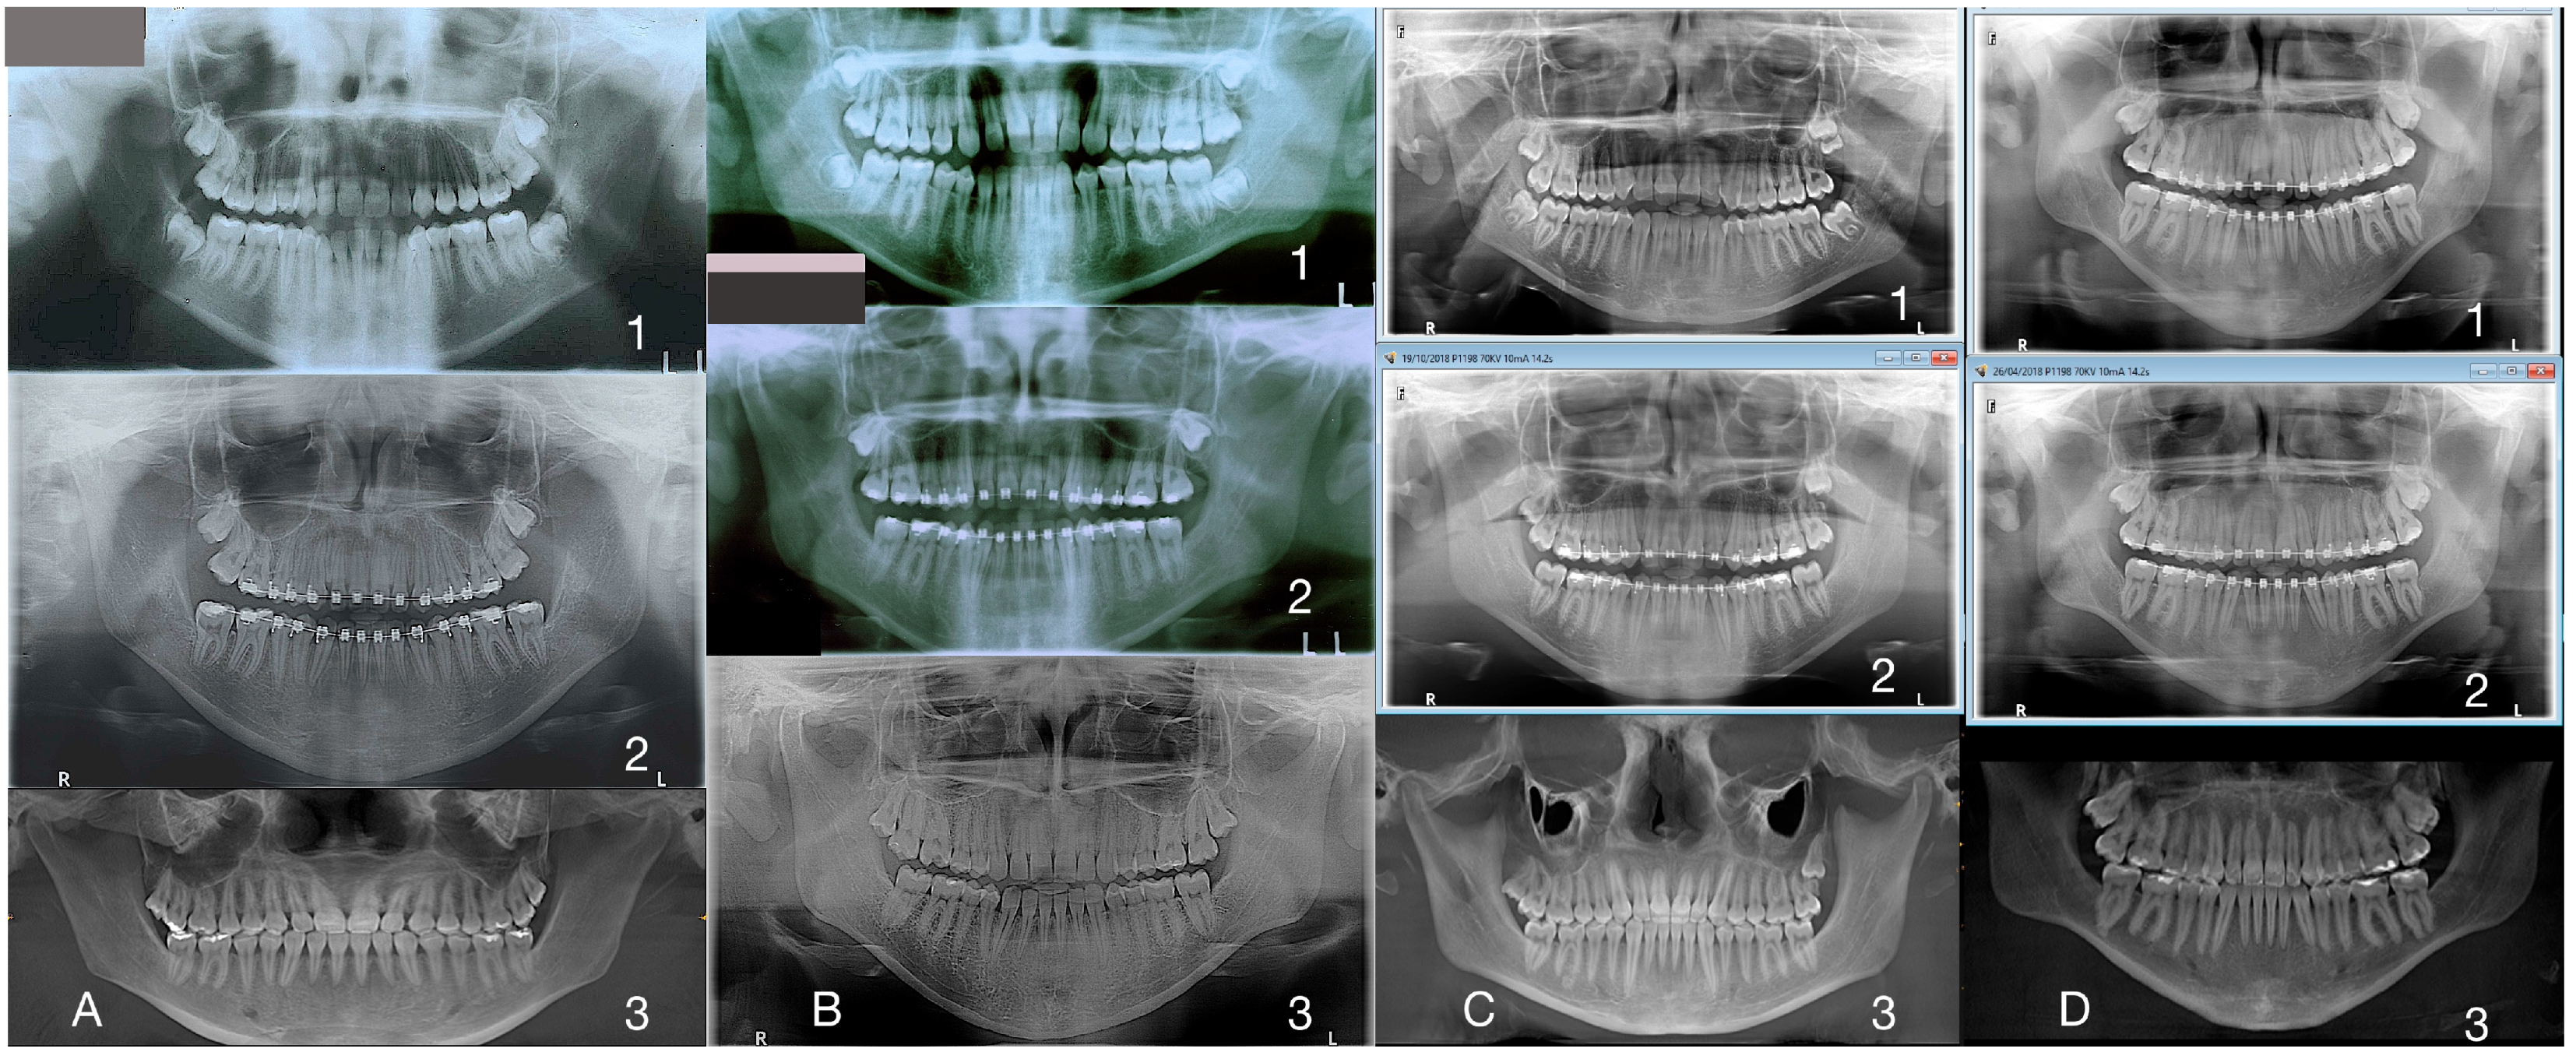

3. The Results of the Treatment